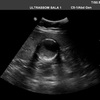

21

Q

A

Cholelithiasis